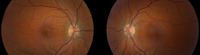

Idiopathic intracranial hypertension

Bilateral disc swelling settled

From the personal collection of Dr M. Wall; used with permission